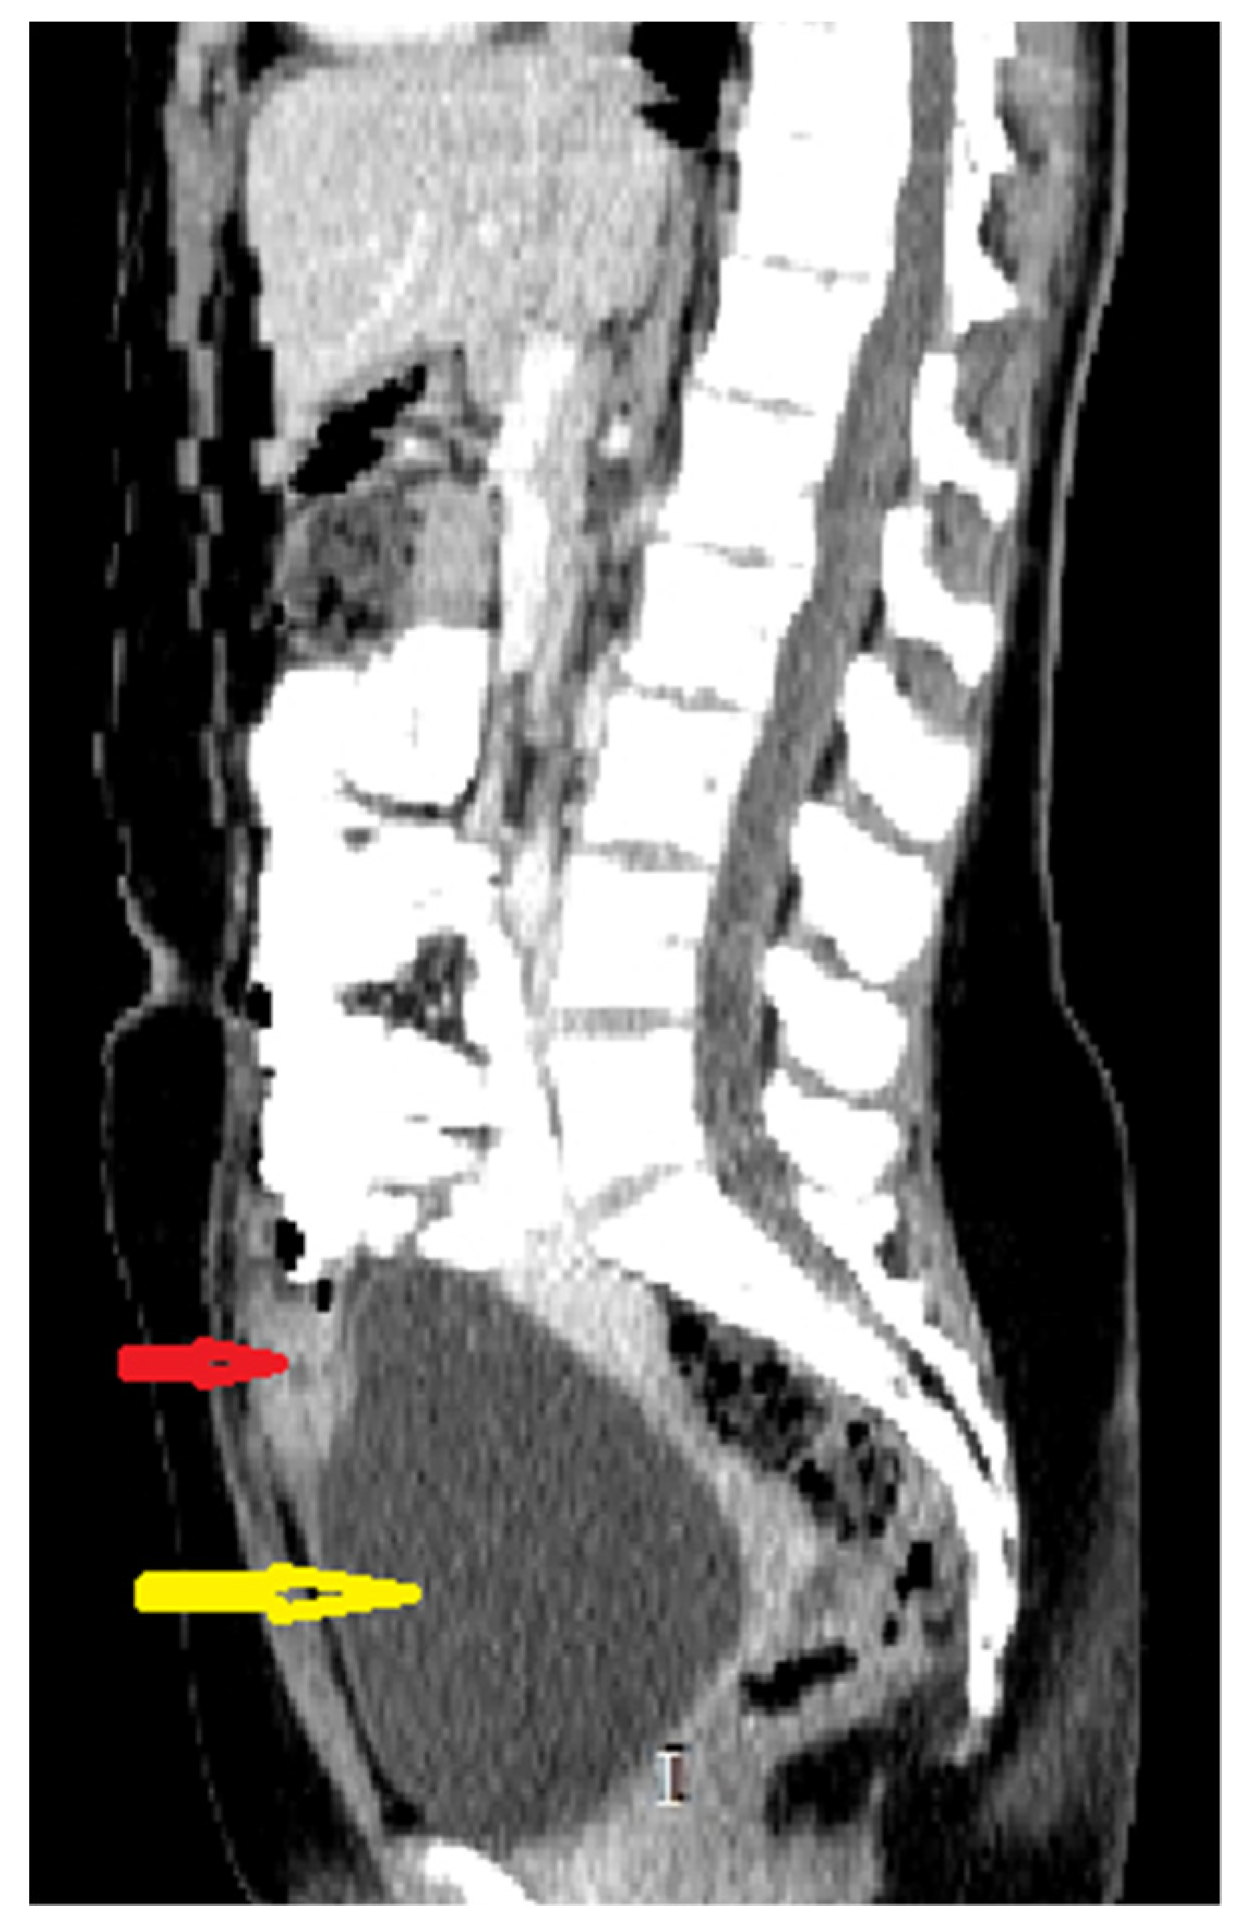

Because the radiologists requested additional investigations, an abdominal–pelvic CT scan with intravenous contrast was performed, adding an intense contrast capture in the periphery of the lesion with edema of the prevesical space (Figure 2 and Figure 3).

Figure 2. Sagittal CT scan reconstruction of abdomen and pelvis with intravenous and oral contrast: red arrow: supposed urachal cyst; yellow arrow: urinary bladder.